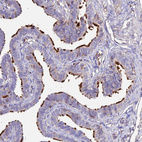

Immunohistochemical staining of human fallopian tube shows strong positivity in cilia of glandular cells.